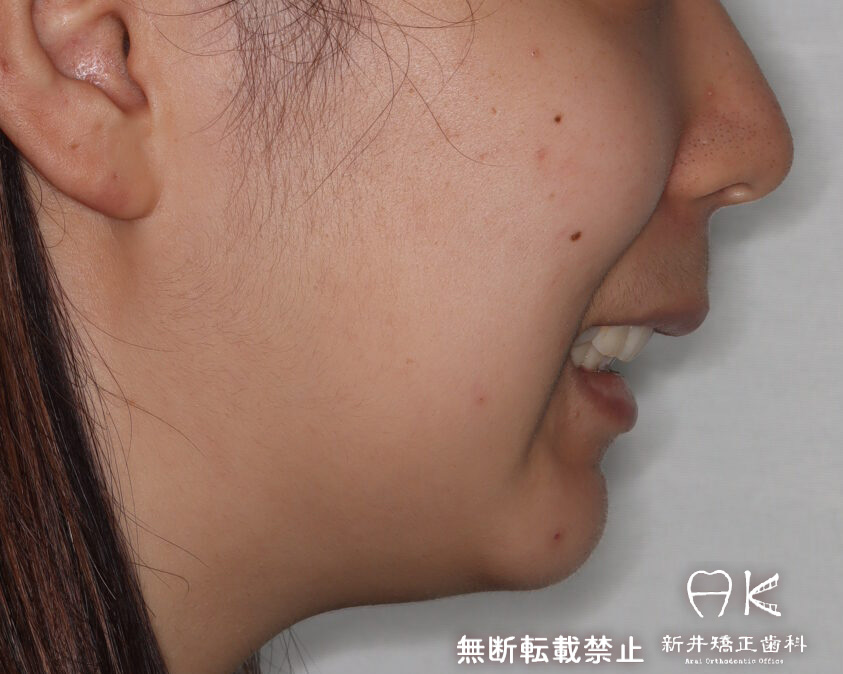

ハーフリンガルでの叢生(ガチャ歯)とすれ違い咬合と口元の突出感の治療(正面と横顔の変化あり)

セファログラムのトレースの重ね合わせ(緑:治療前、赤:治療終了時)

治療前後の解説

| 治療前 | でこぼこしている歯による歯磨きのやりにくさや、奥歯がしっかり咬んでいない鋏状咬合(すれ違い咬合)。 出っ歯による口の閉じにくさ(口唇閉鎖不全)と、正面から見た時のオトガイ部にできる梅干し様のシワやイーラインから飛び出た口元(口ゴボ)。 機能面も審美面も気にしていた患者さんです。 治療中もなるべく装置を目立たせたくないため、ハーフリンガルでの治療となりました。 |

| 治療後 | 上下の歯がお互いにはまり込み、全体的に緊密な咬み合わせになっています。 出っ歯が治り、口元の突出感が改善されて綺麗なEラインを獲得しました。 すれ違い咬合や叢生(歯のでこぼこ)も治って歯磨きがしやすく、嚙みやすい状態になっています。 |